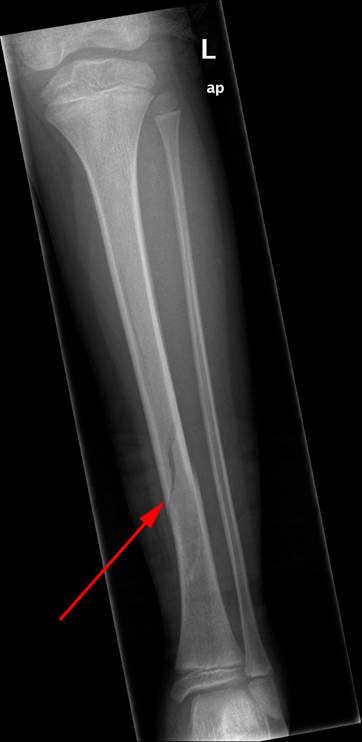

Brud i underbenet kan være isolerede brud af lægbenet eller skinnebenet eller brud, som omfatter begge knogler. Bruddene kan være tvær-, skrå-, spiral- eller knusningsbrud. Dertil kommer træthedsbrud og brud på grund af anden sygdom.

Skråbrud af underarmsknogle

Røntgenundersøgelsen omfatter hele benet, knæet og anklen. Røntgenbilledet vurderes med henblik på, om bruddet kan behandles uden operation.

Særligt spiralbrud eller knuste brud vil ofte kræve operation.